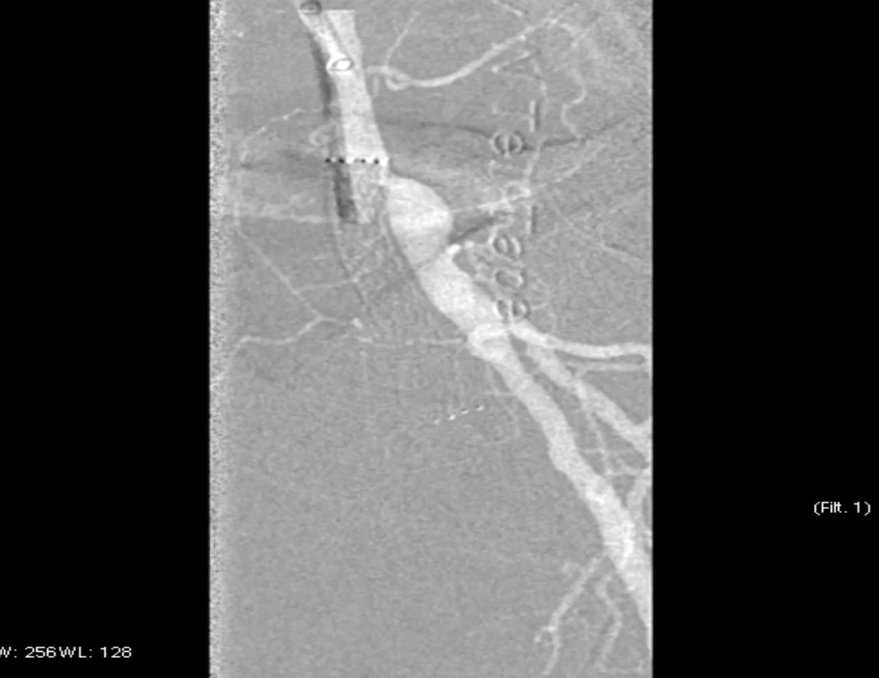

预扩张:先用3mm球囊对病变段预扩张,便于后续器械导入。

保护伞置入:于腘动脉P2段水平放入6mm Spider 保护伞,预防栓塞。

定向旋切:采用新一代Hawk-Plus定向斑块旋切装置进行减容。对于支架内闭塞段,放大图像,确保刀头在可视范围内,反复旋切至接近支架边缘;

对于支架远端病变段,分别采用4个方向各旋切1次,完成初期减容。

器械优势:刀头弧度更大,与血管壁接触面积广,切除效率更高;